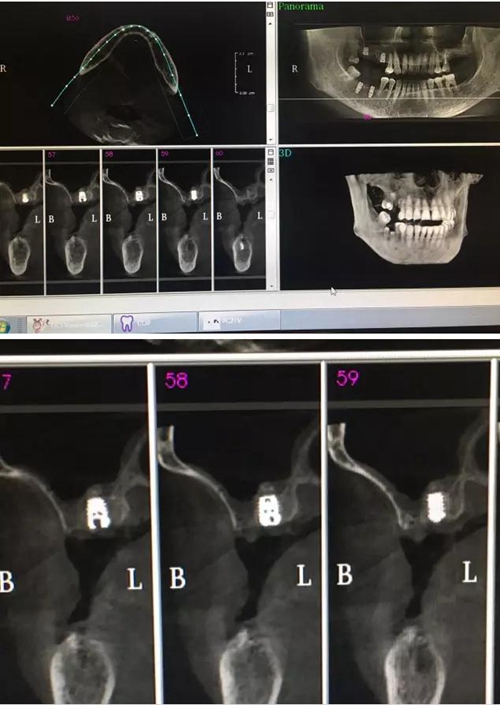

【病例分享】內(nèi)提,用自體骨柱,不用骨粉

1.jpg